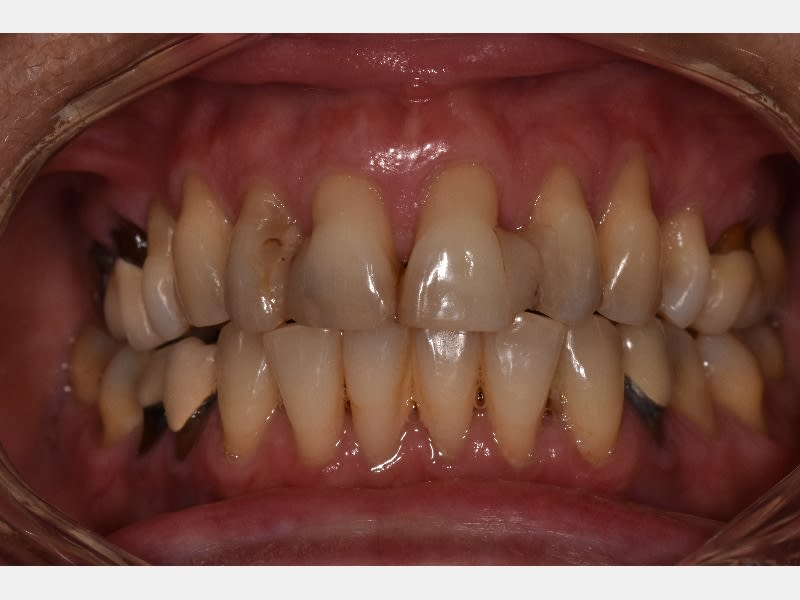

J'ai vu cette patiente de 60 ans ce matin et je sèche un peu sur le traitement, surtout par rapport aux récessions antérieures, elle a surtout une demande esthétique au niveau de la zone antérieure maxillaire.

La parodontite est stabilisée pas de poches au sondage, mais la contention antérieure qui a été faite il y a 20 ans suite à un traitement ortho-paro vieillie mal.

Des avis? peut on gérer ce cas avec en recouvrant les récessions avec de la mucco gingivale et ensuite des recontitutions? ou alors fausse gencive céramique?

T’as pas lésion osseuse angulaire , sur les Canines notamment ? Et ça saigne pas en bas , sur ? Vas y mollo , ça m’a l’air stable du tout la paro , vu d’ici..

Même avis sur la paro qui semble limite. Par contre, un joli bridge de contention 3-3 en zircone donnerait un joli résultat esthétique, la fausse gencive c'est rarement génial, sauf à créer des zones de rétention de plaque.

Point de vue morpho, 11 21 seront légèrement raccourcies, et la récession masquée de ce fait, et les embrasures seront facilement fermées...

Je suis d'accord pour le bridge ou des facettes mais oublie la fausse gencive c'est moche. Juste des dents un peu plus large et plus longues, fait un wax up et un essayage avec mockup. Pour moi les facettes avec minimum de délabrement seraient le mieux mais si des dents sont mobiles bridge qui servira de contention sera une solution acceptable.

Je veux bien me faire pendre si en M et D des incisives supérieures on a pas de poches.

Et si tu fais des couronnes, ça va lui faire des sacrés chicots hyper longs. À moins de bien lui raboter tout ça.

Et enfin y a un diastème de 5 mm entre 21 et 22. Ce qui veut dire que sur les futures couronnes il y aura des couronnes plus larges à gauche qu’ à droite.

Tu as une alvéolyse périphérique de presque 50%, associée à des lésions infra osseuses, dont au moins une majeure en palatin de 12, tout cela n'étant masqué que parce que le biotype parodontal est favorable. Ce n'est pas grave, si le boulot est bien fait elle pourra le mener au bout, mais à moins d'avancées majeures en paro dont je n'ai pas eu connaissance, on ne fait pas encore repousser l'os, et quand on a de la gencive à 5mm au-dessus du niveau osseux, ça s'appelle une poche.